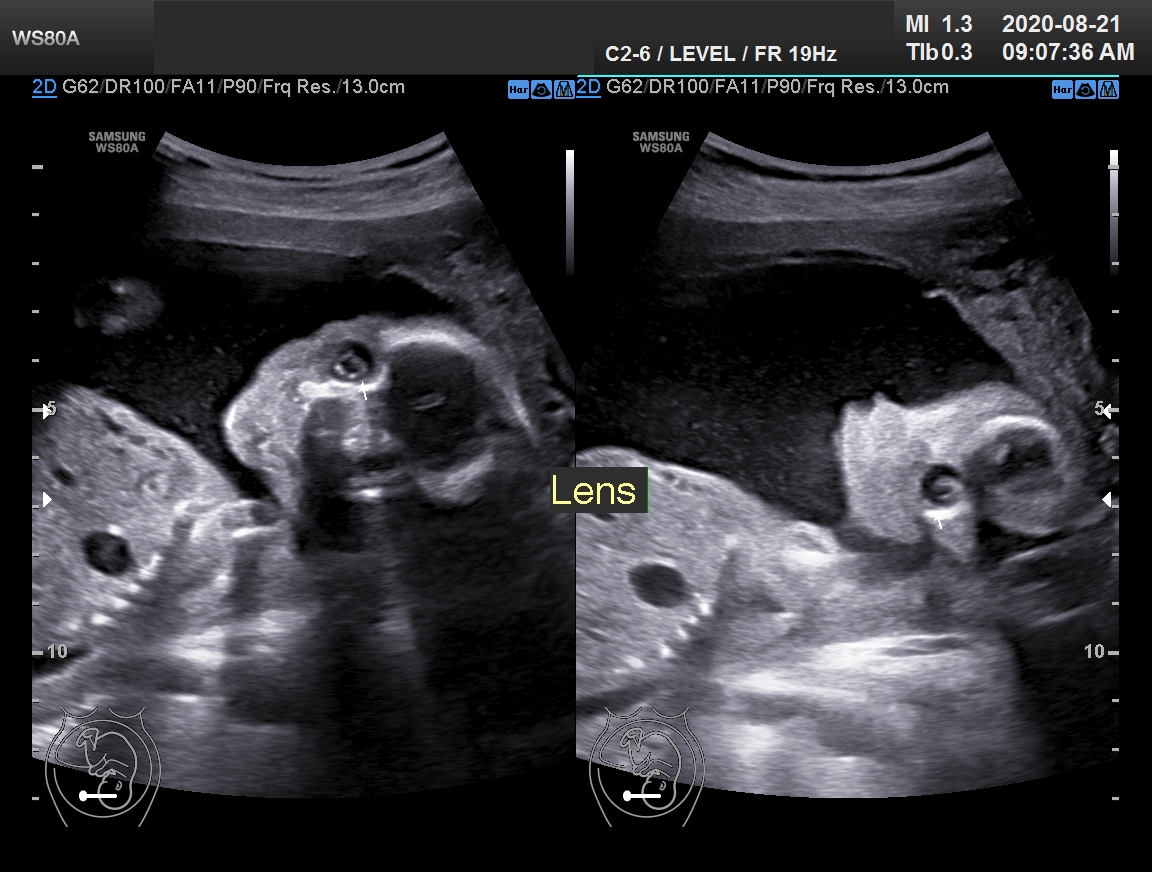

Congenital dacryocystocele is a benign solitary mass

arising from narrowing or

obstruction of the nasolacrimal system during natal development.

Its prenatal diagnosis, using sonography,

is straightforward. CT and MRI are of benefit

only if the diagnosis is unclear.

It is usually detected during the third trimester.

Many lesions resolve spontaneously or after minimal intervention.

We report a case of a healthy male neonate with a

congenital dacryocystocele, which was diagnosed pre-natally.

Further examination did not reveal

any other pathological findings and

demonstrated normal fetal facial anatomy